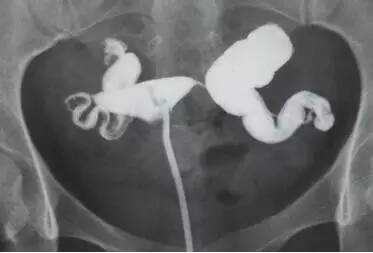

(图:HSG示正常输卵管)

— 输卵管梗阻?

目前临床常使用输卵管造影来评估女方的双侧输卵管通畅情况。在X线透视下,向子宫腔内缓慢的注入造影剂(碘油或碘水),观察造影剂在双侧输卵管腔内的显影、溢出,以及最后弥散至盆腔内的情况。有时患者一侧输卵管显示非常通畅,而另一侧则未显影,这时就需要仔细判读了,因为可能发生误判。有几个要点以供参考:

在输卵管显影的形态上,常常被描述成“扭曲”而不通畅,其实这是不太严谨的。盆腔X线透视,是将一个三维立体的盆腔内容,投影到一个二维平面的图像。输卵管是一个狭长而柔软的管性器官,在盆腔空间中的位置可以是各种走向的。如果和输卵管走向偏垂直时,X光图像就应该是投射成“扭曲”形状的,并不能确定为输卵管粘连成团的证据,需要结合其他临床指标判断。

输卵管如果显影为两端“上举”向腹腔方向,也可能是仰卧体位使得盆腔器官被腹腔脏器牵引,如果站立后输卵管可能就复位下降了。不能说明输卵管一定粘连在两侧盆腔侧壁,这是一种有点武断的想象,需要结合其他临床指标综合分析其可能性。